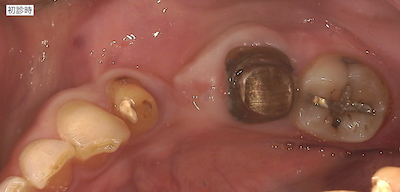

ブリッジが外れたと患者さんがご来院されました。

手前の支台歯は神経は残っていましたが、奥の支台歯は神経を抜いてかなりの時間が経過していると考えられました。ブリッジにすると、清掃性や咬合負担を考えた時に、次に外れる時は奥の歯は保存不可能になっていると推察しました。今は1本の欠損ですが、ブリッジにすると近い将来奥歯がダメになった時には2本分の欠損となります。欠損部にインプラントを行い、単冠処理した方が咬合負担が減り清掃性も良くなりベターであることを説明し、患者さんのご希望に治療計画書を作成しました。